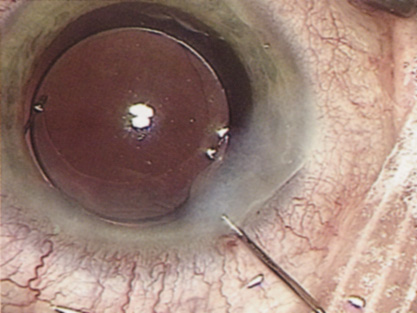

Despite numerous incision choices, one key factor is recommended for all cataract incisions: The incision should be self-sealing. A self-sealing incision decreases the risk of catastrophic expulsive hemorrhage if significant positive pressure develops for any reason. If positive pressure develops at any time during the procedure, simple removal of the instrument should prevent expulsion of the intraocular contents. Additionally, if properly placed and constructed, a self-sealing incision obviates the need for a suture, thereby avoiding suture distortion of the wound and induced astigmatism. Closure of the incision, regardless of incision type, should ensure that intraocular pressure or external pressure at the posterior lip of the incision, or elsewhere, will not cause wound leak. If leakage occurs, then stromal hydration or suture placement may be necessary. Whenever placing a suture across a cataract incision, the ocular tension should approximate normal pressure before tightening the suture. Doing so helps prevent the surgeon from overtightening the suture, which would induce astigmatism. ANTERIOR CAPSULOTOMY One of the most beneficial techniques developed over the last decade is capsulorrhexis. A continuous curvilinear anterior capsular opening helps prevent intraoperative and postoperative complications. With capsulorrhexis, mechanical strength of the capsular opening is superior to that in a can-opener capsulotomy; thus, a tear to the posterior capsule with subsequent vitreous loss is much less likely.96 Capsulorrhexis allows for nuclear manipulation with less risk of posterior capsule rupture. Cortex removal is made easier as well, because it becomes easier to differentiate cortical material from anterior capsule. Should a posterior capsular tear occur, sulcus fixation is more likely attainable with the presence of a clearly visible residual anterior capsular rim. Placement of both IOL haptics into the capsular bag is more certain with capsulorrhexis because the surgeon can more easily visualize the haptics gliding beneath the anterior capsular rim. Capsulorrhexis can be performed with a cystitome, capsulorrhexis forceps, or combination-type instruments. Regardless of which instrument is used, several principles can help the surgeon successfully complete capsulorrhexis. It is important to maintain the anterior chamber, because making the chamber shallow increases tension on the zonules and causes the tear to run peripherally. The authors recommend the use of a viscoelastic agent for maintaining chamber depth and, of course, for endothelial protection. Therefore, if the tear begins to run peripherally, the surgeon should redeepen the anterior chamber before attempting to redirect the tear. Additionally, folding the capsule margin can aid the surgeon in redirecting the tear more accurately (Fig. 10).